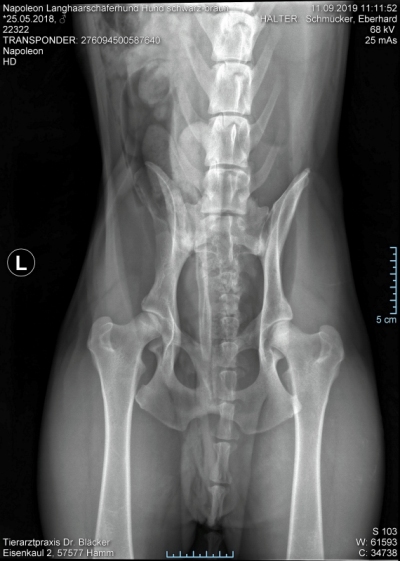

Röntgentermin am 11.09.2019

Hier sind  HD-ED Aufnahmen von unseren “Napoleon von KaTum”   alles Top

Keine HD und kein ED,LÜW ist alles gut